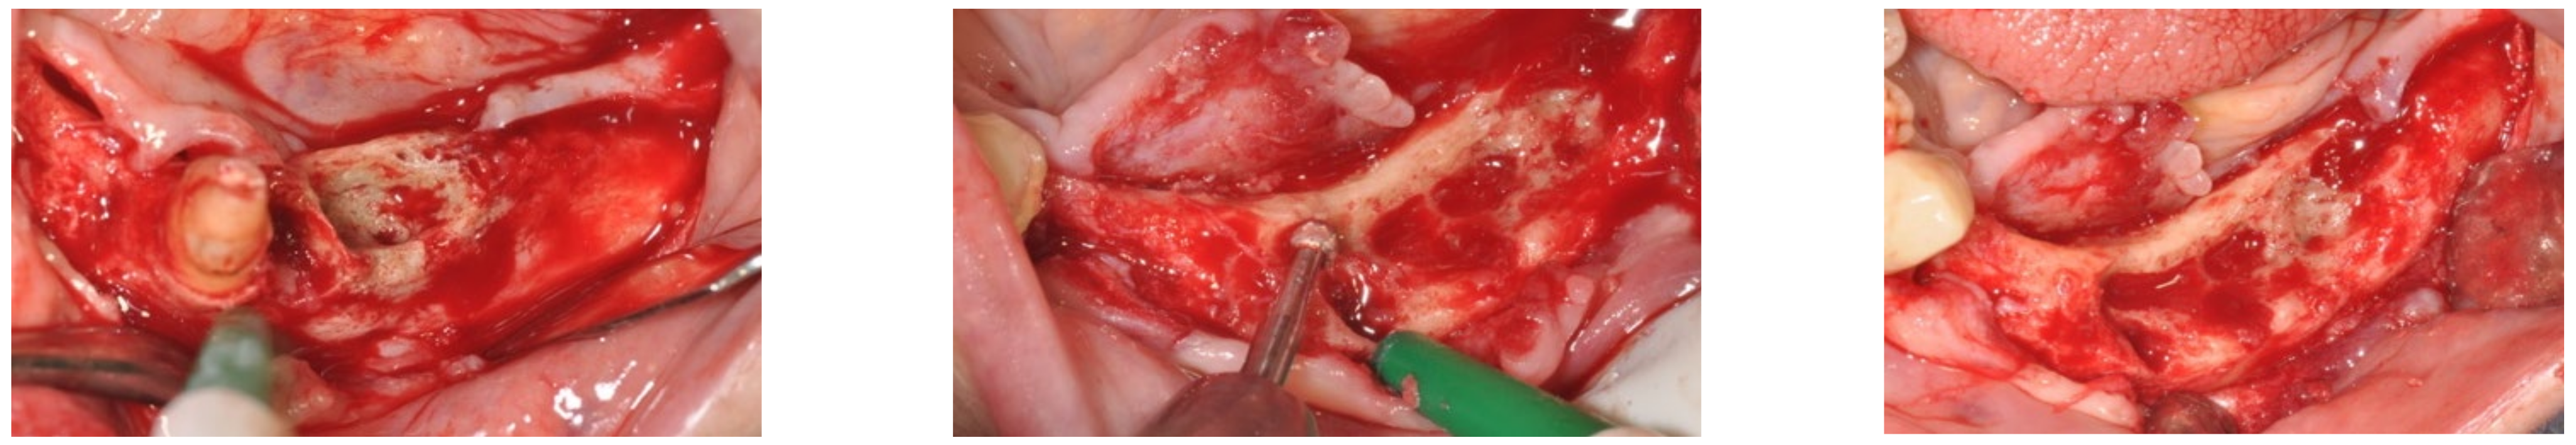

3.1. Clinical Case 1

3.2. Clinical Case 2

3.3. Clinical Case 3

3.4. Clinical Case 4

3.5. Clinical Case 5

3.6. Clinical Case 6